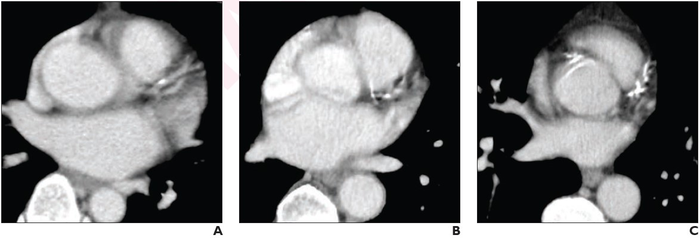

(A) mild, (B) moderate, (C) severe CAC on non-gated contrast-enhanced chest CT. Image courtesy of American Roentgen Ray Society (ARRS), American Journal of Roentgenology (AJR)

Hanneman and colleagues’ retrospective study included 260 patients (mean age, 60; 158 male, 102 female) who underwent both non-gated chest CT (contrast-enhanced in 116 patients; non-contrast in 144 patients) and cardiac calcium-score CT within a 12-month interval. A cardiothoracic radiologist visually assessed CAC on chest CT using an ordinal scale: absent, mild, moderate, or severe.

Ultimately, visual ordinal assessment of coronary artery calcium on both contrast-enhanced and non-contrast non-gated chest CT has high sensitivity (83% vs 90%, p=.20) and specificity (100% vs 100%, p=.99), prognostic utility (HR 4.5, p=.02 and HR 3.4, p=.003, respectively), and excellent interobserver agreement (κ=0.89 and κ=0.95, respectively).